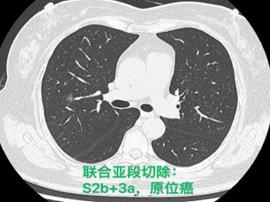

常规腔镜方面,以胸部肿瘤外科为主,开展肺叶、肺段、复合肺段/亚段切除、解剖性肺切除、袖状切除等手术,包括单孔到多孔等各种入路。在北京市较早开展微创食管癌切除,积累了丰富的经验。纵隔肿瘤方面,开展包括剑突下及其他入路胸腺切除、胸腺扩大切除,无名静脉成型等。同时结合锚丝定位、术前三维重建技术和荧光腔镜技术使手术安全高效。

目前主流的胸外科微创手术业务我科已达到全覆盖。包括但不限于:胸腔镜下肺叶、肺段、亚段、联合亚段、全肺、肺袖状切除术;单孔胸腔镜微创手术,Hook-Wire定位小结节精准切除手术,微创胸腹腔镜联合食管癌切除术,剑突下纵隔肿物切除术,达芬奇机器人辅助各类手术等几乎所有的胸外科先进微创的手术方式。

各类联合亚段切除术